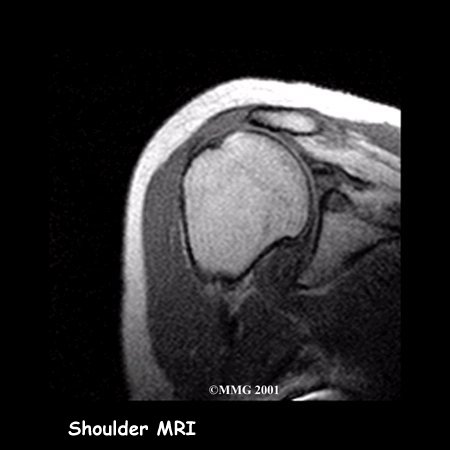

Your doctor may ask you to have a magnetic resonance imaging (MRI) scan.

An MRI scan is a special imaging test that uses magnetic waves to create pictures of the shoulder in slices. The MRI scan shows tendons as well as bones. This test is painless and requires no needles or injections.